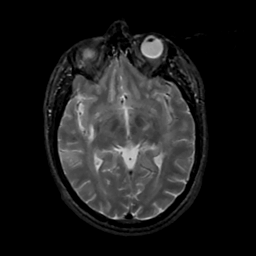

MR Study #15, June 9, 1991 -- Slice #23